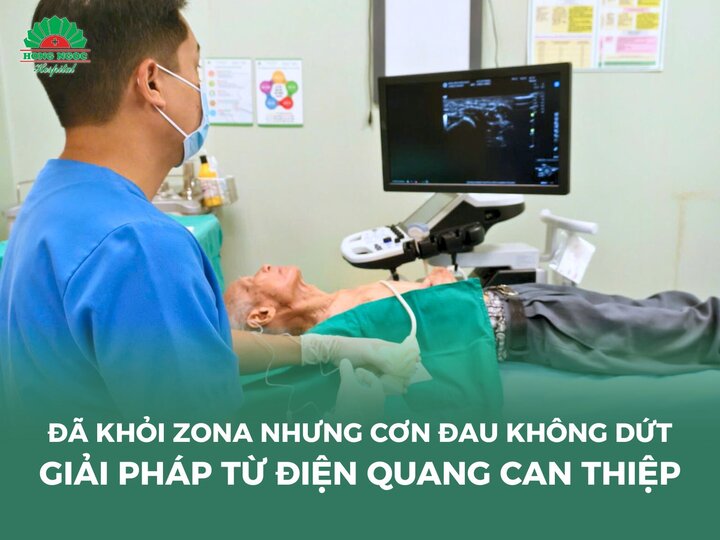

Sử dụng thuốc kháng sinh theo kết quả kháng sinh đồ, sử dụng sớm và đủ liều. Chỉ rạch dẫn lưu mủ dưới sự hướng dẫn của các phương tiện chẩn đoán hình ảnh như siêu âm. Cũng cần loại bỏ dị vật bên trong ổ áp xe nếu có.